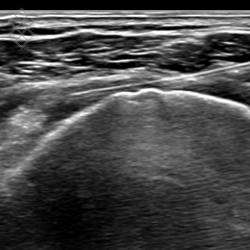

Échographie de l’Épaule

La durée de l'examen est d'environ 20 minutes. Il est indolore et est réalisé par un médecin radiologue.